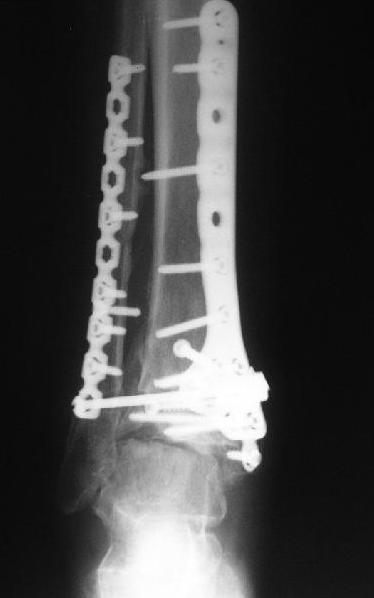

Обратилась женщина, 25 л. 8 мес. назад в одной из больниц сделан

остеосинтез пилона. На сегодня ходит без дополнительной опоры, хромая

на поврежденную ногу. Движения в голеностопном суставе еще есть.

Снимки в приложении.

Вопрос - что делать? Замыкать сустав пациентка пока не настроена

(наверно, получится настроить, если задаться такой целью). Нет ли

смысла попытаться сделать какую-то восстановительную операцию?

Допустим, получится устранить подвывих, восстановить межберцовые

соотношения - это что-то хорошее надолго даст? Или упросто убрать

"железо", и этим ограничиться, пока сама не придет за артродезом?

Есть ли здесь смысл пытаться организовать эндопротезирование? В

смысле, доступные сейчас протезы применимы в этой ситуации?